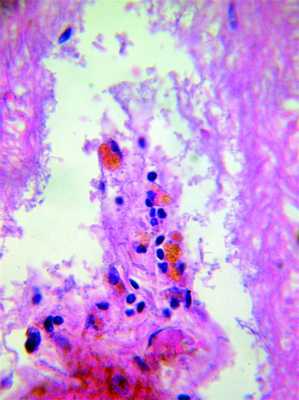

При иммуногистохимическом исследовании в коре головного мозга в изучаемой группе определено значительно меньшее число GFAP-положительных клеток и их отростков — в 1,2—1,8 раза, чем в группе с ЧМТ без фоновой ГБ, особенно в белом веществе в сроки от 2 до 14 сут [6—8] (рис. 3, на цв. вклейке), Рисунок 3. Сравнительное распределение астроцитов по периферии очага ушиба полушарий большого мозга. Мужчина, 68 лет. Окраска GFAP, докрашено по Нисслю. Ув. 400. а — распределение астроцитов на 5-е сутки после возникновения очага при отсутствии в катамнезе артериальной гипертонии. Рисунок 3. Сравнительное распределение астроцитов по периферии очага ушиба полушарий большого мозга. Мужчина, 68 лет. Окраска GFAP, докрашено по Нисслю. Ув. 400. б — одиночный астроцит в периконтузионной зоне на 5-е сутки на фоне гипертонической болезни. в связи с этим можно говорить о том, что в условиях циркуляторной гипоксии при ГБ пролиферация астроцитов явно недостаточна для замещения дефектов белого вещества, образовавшейся деструкции миелина и олигодендроглии [9].